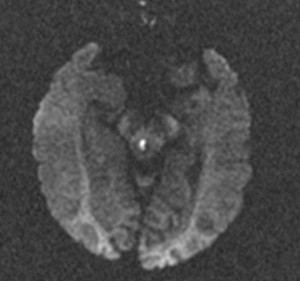

RM Difusión: La técnica de difusión por resonancia magnética se usa para caracterizar patologías intracranealess, detectando los cambios en el movimiento libre de las moléculas de agua en los tejidos. Esos cambios microscópicos se producen en cualquier proceso patológico y se puede traducir en un aumento o disminución del movimiento de las moléculas (difusión). Su popularidad se basa en su rapidez, sencillez en la interpretación y en la capacidad de demostrar alteraciones del encéfalo antes incluso de que aparezcan otros cambios evidentes por tomografía computada (TC) o secuencias convencionales de resonancia magnética (RM).